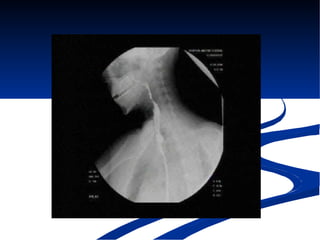

El documento habla sobre la anatomía y trastornos del esófago. Menciona las condiciones como el esófago de Barrett, el divertículo de Zencker, la acalasia y el cáncer de esófago, describiendo sus síntomas y tratamientos. Explica que el esófago de Barrett aumenta el riesgo de cáncer esofágico y que la acalasia se caracteriza por la hipertrofia del esfínter esofágico inferior y la ausencia de peristaltismo. También cubre factores de riesgo